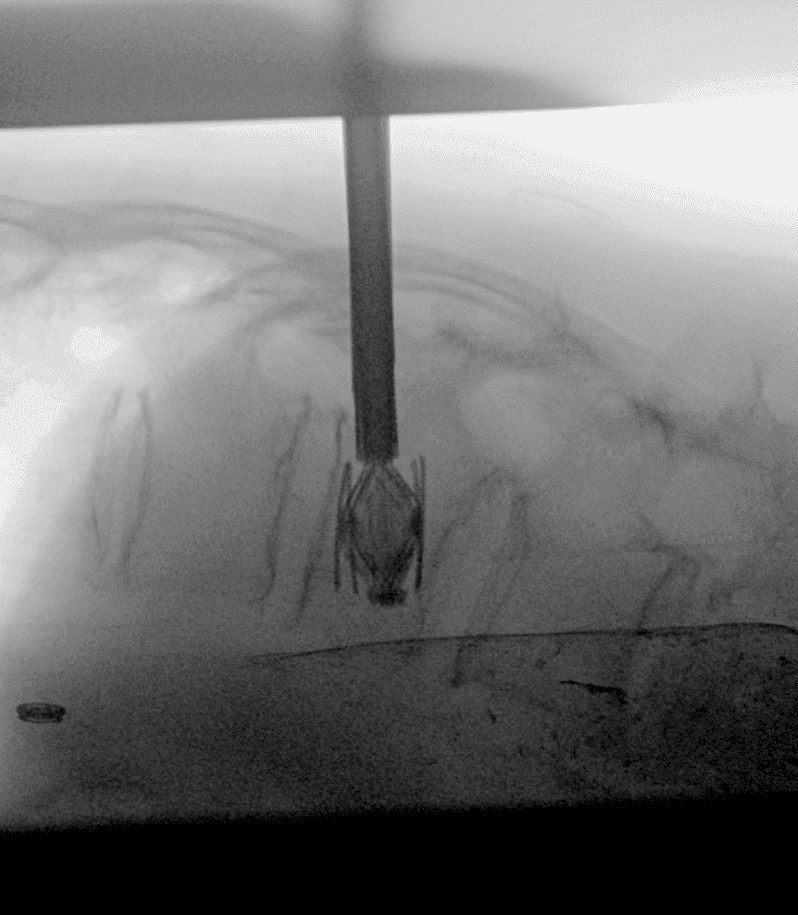

Guidage par imagerie

À l’aide de la fluoroscopie et/ou du scanner, l’équipe médicale guide avec précision une aiguille jusqu’au site de la fracture, en s’assurant d’éviter les structures sensibles.

Insertion et déploiement de l’implant

L’implant SPINEJACK est introduit dans le corps vertébral. Une fois en place, il est progressivement déployé pour redresser la vertèbre et restaurer sa hauteur, améliorant ainsi la posture et réduisant la douleur.